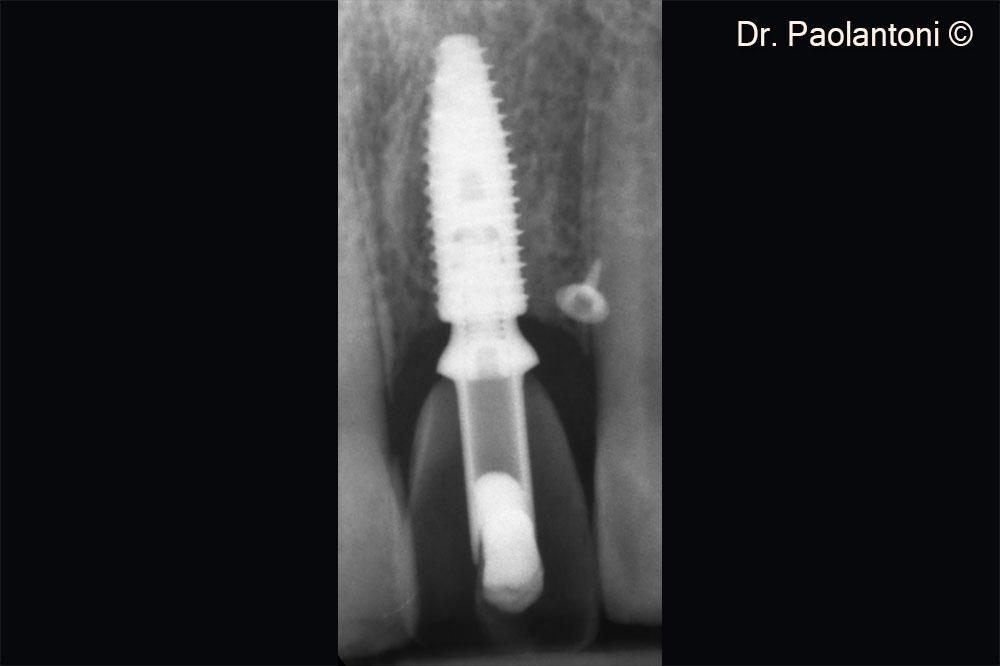

Rx control